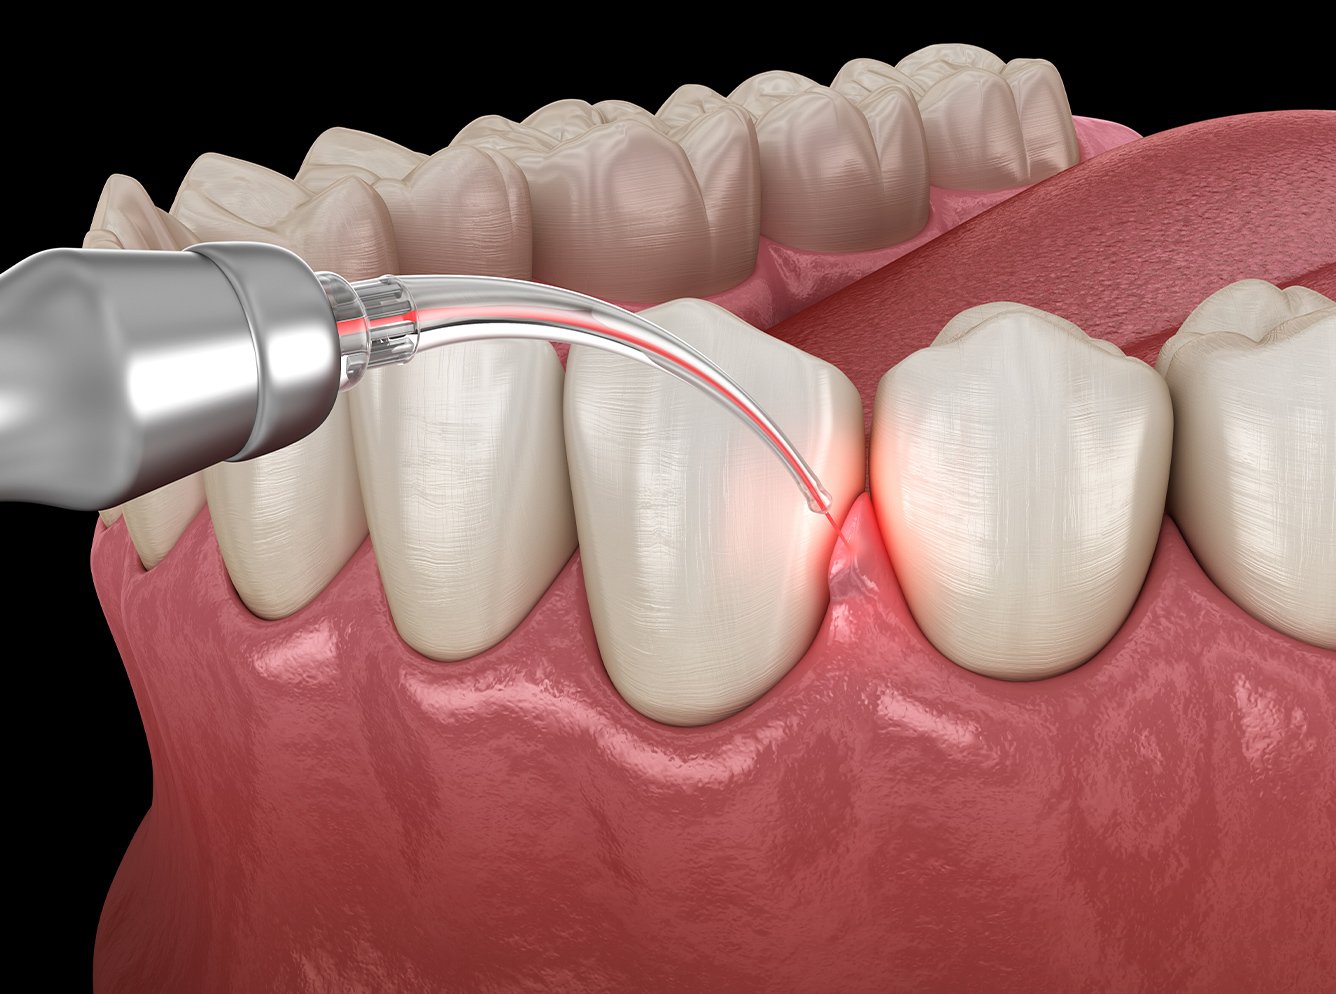

HIGH FREQUENCY 歯周病の高周波治療とは

そもそも高周波治療とは、高周波を当てることにより振動を起こし、その振動による摩擦で熱を発する治療法です。高周波によって細菌や悪い組織の殺菌や、自然治癒力を高めることができ、治療期間を短縮することができます。

歯周病においては高周波治療器から発する高周波電流により発生した熱で、歯周ポケットの奥まで侵入した歯周病菌を殺菌・除去します。